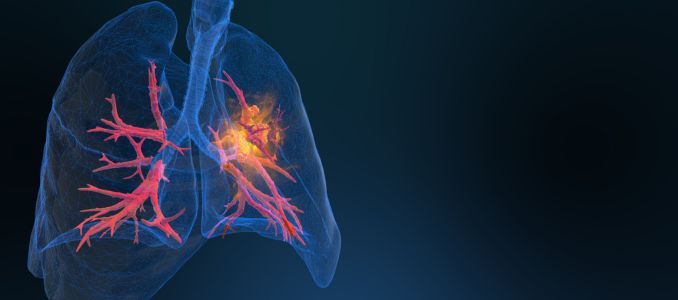

NIOSH is offering free screenings to help coal miners identify black lung disease early and track respiratory health impacts from coal mine dust exposure.

The screenings are offered through the National Institute for Occupational Safety and Health (NIOSH) as part of the Coal Workers’ Health Surveillance Program, which provides confidential testing for current and former coal miners. Black lung, also known as coal workers’ pneumoconiosis, is a serious and irreversible lung disease caused by prolonged exposure to coal mine dust.

Screenings may include chest X-rays and breathing tests that help identify early signs of lung disease. The program operates through approved medical facilities and mobile health units that travel to mining communities to increase access to testing.

Health officials say early detection is critical, as black lung can worsen over time and lead to severe breathing problems and disability if exposure continues.